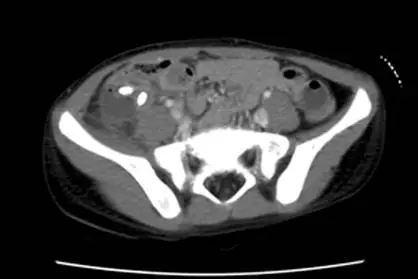

12 歲男生因急性發作腹痛、嘔吐、發燒而至急診室,注射對比劑後的下腹部電腦斷層掃描影像如圖,則最可能之原因為 何? 圖片

圖片為注射顯影劑後的下腹部橫切面電腦斷層(contrast-enhanced CT, CECT):

• 右下腹(RLQ)可見一個密度不均的團塊狀病灶,周邊有顯影劑環形強化(rim-enhancing)的液體積聚,符合腹膜周圍膿瘍(periappendiceal abscess)

• 病灶周邊脂肪組織呈現條紋狀密度增高(fat stranding),代表周邊腸繫膜及脂肪有發炎浸潤

• 右下腹結構紊亂,正常闌尾結構無法辨識,提示闌尾已穿孔

• 可見少量腹腔游離液(free fluid)

• 左側及下方可見正常的髂腰肌(iliopsoas muscle)及兩側髂骨(iliac bone)

• 無腎結石高密度鈣化影、無膽囊結構異常、無蟲卵鈣化,排除腎結石、膽結石及血吸蟲病